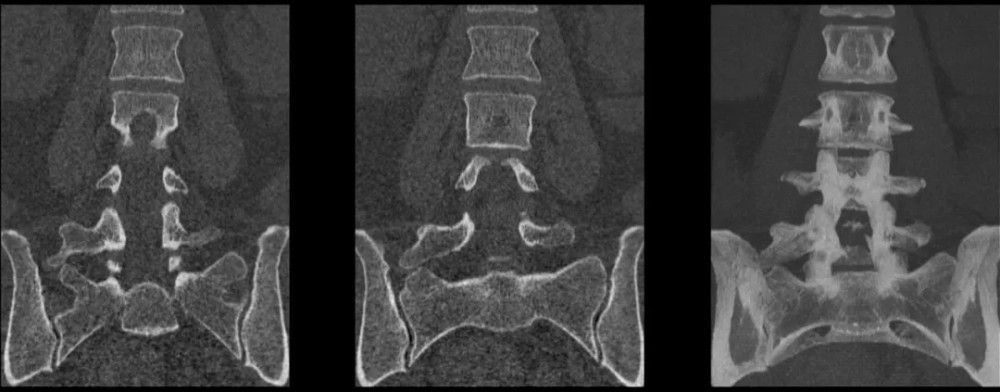

文章插图

右侧 L5 横突肥大 , 故可以诊断为移行椎 Ⅰa 型;

CT 图像重建证实 L5 椎体右侧横突肥大 , 间隙正常 。